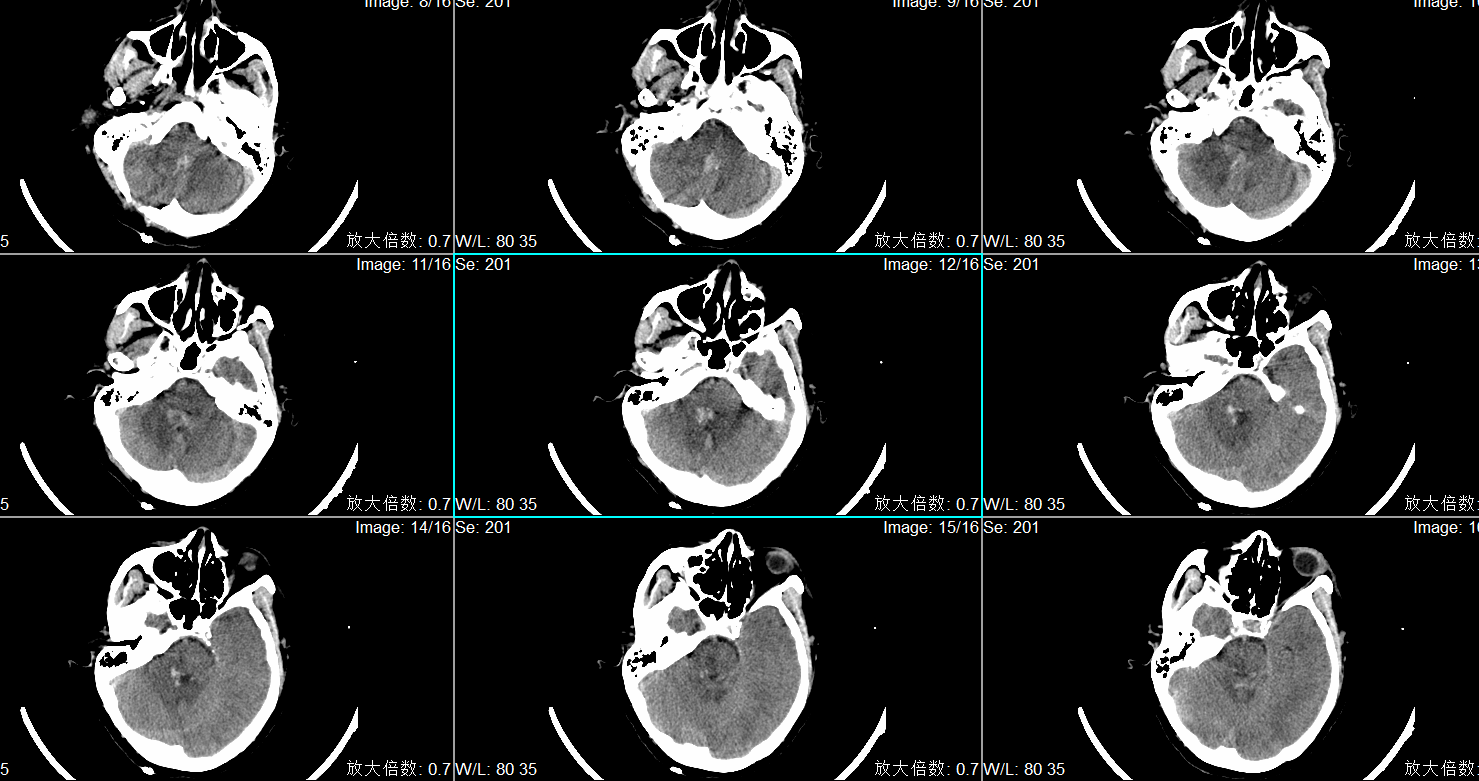

入院头CT显示小脑蚓部出血破入第四脑室、第三脑室及第四脑室。

入院诊断为:1.小脑蚓部出血 2.高血压病3级(极高危)3.吸入性肺炎。

术前头CT